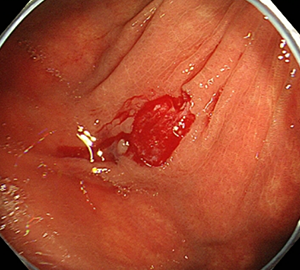

ごくまれに出血や穿孔などの偶発症を起すことがあります。また、下剤のために腹痛や出血、穿孔を起こすこともあります。出血がみられたり、腹痛を認めましたら、すぐに関東労災病院内視鏡センターにまでご連絡ください。入院や緊急の処置・手術が必要になることがあります。なお、大腸内視鏡検査および治療に伴う偶発症発生頻度は全国集計(2008年から2012年の5年間)で0.011%(9,091人に1名の割合)でした。

内視鏡を使った治療法には、スネアと呼ばれる金属の輪を病変部に引っ掛け、高周波電流を流して切り取る方法(内視鏡的粘膜切除術;Endoscopic mucosal resection:EMR)や、専用の処置具を使ってより大きな病変を剥がす内視鏡的粘膜下層剥離術(Endoscopic submucosal dissection: ESD)などがあります。

EMRは治療が比較的短時間ですみますが、小さな病変でも1回の切除で取りきれない場合があり、治療後の再発の頻度が5%程度認められます。

ESDは2cmを超える大きな病変でも、病変を分割することなく一括で切除するために開発された治療法です。専用のナイフを用いて病変の端から少しずつ確実に剥離して一括切除します。一括切除することで病変の正確な評価が可能となり、癌が取りきれたか、どこまで深く浸潤しているかなどを判定し再発リスクや追加治療の必要性が適切に判断出来ます。

1回の切除で完全な切除ができますので、治療後の再発はほとんどありません。

ESDの入院期間は病変の大きさや手術時の状況にもよりますが概ね7-9日で行っています。